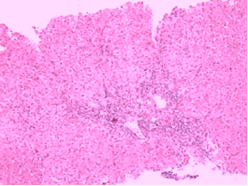

西医病因

脾脏是由结缔组织支架、淋巴组织、血管和淋巴管以及造血和单核-巨噬细胞系统的细胞所共同组成。脾脏分为白髓和红髓两部分,中间有过度区,即边缘带,为红髓接受动脉血区域(图1)。白髓是由密集的淋巴组织构成,是T淋巴细胞的主要分布区,与淋巴小泡的结构相似,但其血循环丰富。从小梁动脉分出的小动脉,其周围有大量的淋巴硝,称为淋巴鞘的中央动脉。淋巴鞘内有密集的淋巴细胞和浆细胞。中央动脉与其分支小动脉呈垂直位,因此分支小动脉内大部分是血浆,血细胞很少,有利于脾脏发挥免疫作用。血液中的抗原物质经过分支小动脉和毛细血管直接与淋巴鞘内的淋巴和浆细胞接触,刺激生成更多的免疫活性细胞。由于抗原刺激,白髓中可出现生发中心,其内部有分化增殖的B细胞,可产生相应抗体。